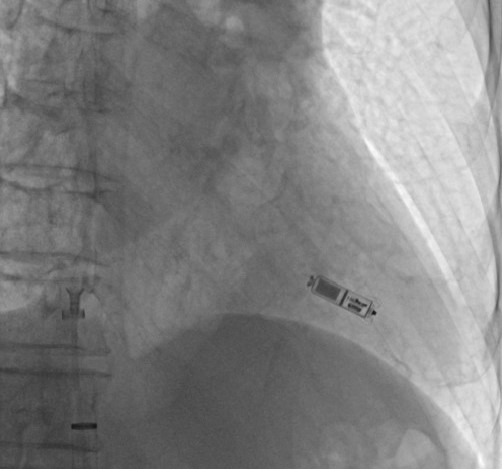

23日下午,陈步星主任带领心血管科起搏与电生理团队,在局部麻醉后,通过右侧股静脉穿刺,将起搏器植入右心室。何爷爷在整个过程中始终保持清醒状态,约30分钟左右手术顺利完成(图2,3,4,5)。术后何爷爷恢复顺利,第二天便即可自由活动。

图3 Micra植入右心室腔